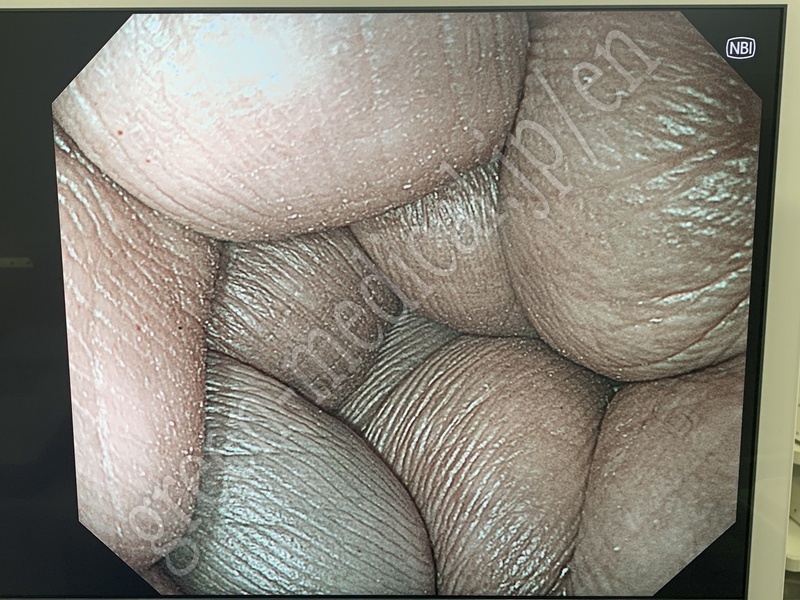

Video System Center EVIS X1 CV-1500

EVIS X1 CV-1500